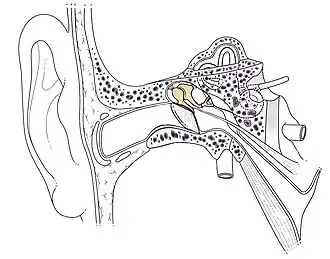

Anatomy gallery

Location of the ossicular chain in the ear

Location of the ossicular chain in the ear -